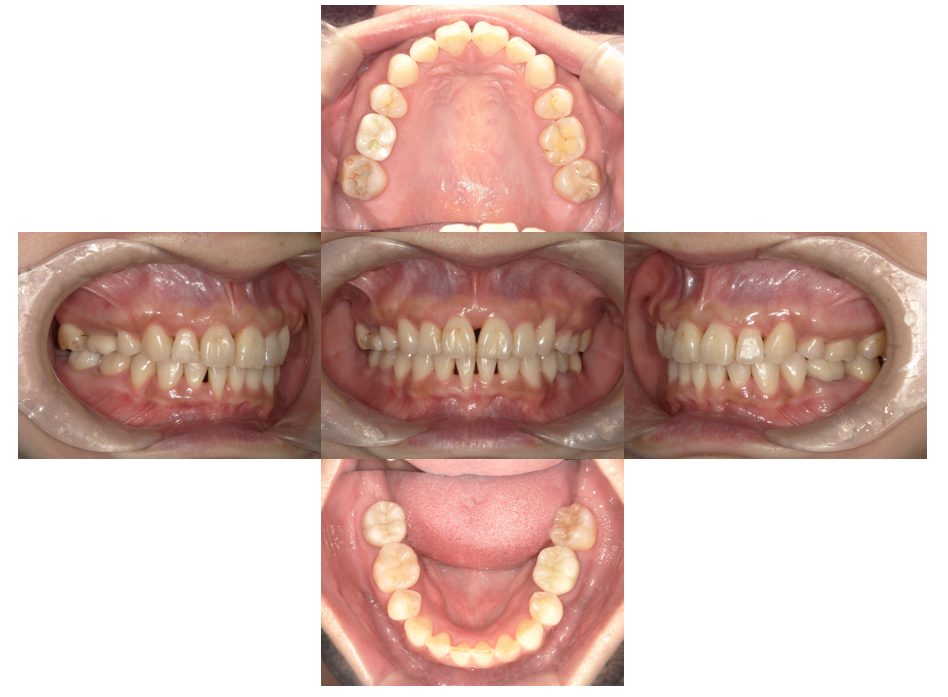

外科矯正治療・インプラント治療の症例紹介(三隅歯科クリニック)

三隅 賢祐(三隅歯科クリニック)

症例詳細

| 主訴 | 20代女性 矯正治療希望。治療途中の歯もあるので治したい。左顎関節が痛い。 |

| 治療内容 | 矯正治療を行いました。 |

| 治療費 | 1,400,000円(税込み) |

| 治療期間 | 3年(矯正治療期間 2年半) |

| 治療回数 | 40回 |

| 想定されたリスク | 顎骨の変形があったので、全身麻酔下による外科処置が必要になり、身体的、精神的負担が増す可能性がありました。 清掃状況によっては矯正中にむし歯が発生するリスクがありました。 |